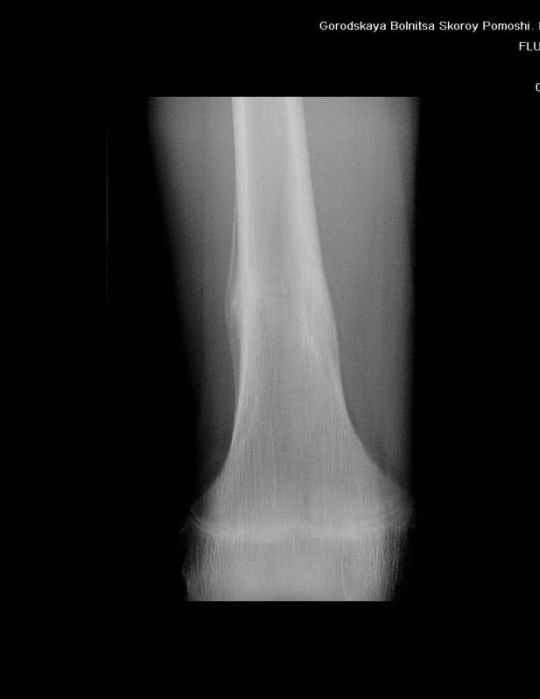

Анамнез практически никакой: в следствие травмы (растяжение связок коленного сустава) от 07.11.2004 выполнены Rg-граммы в травмпункте и обнаружено опухолевидное образование. Первичные Rg-граммы я не публикую, так как они заметно худшего качества, да и динамики за прошедшие три недели не отражают. Болевой синдром купирован в течение трёх дней. В настоящий момент мальчика ничего не беспокоит. Ходьба не нарушена, опухоль пальпируется с трудом по задней поверхности в н\3 правого бедра, пальпация безболезненна, объем движений в суставах правой нижней конечности полный и симметричный. Кожа над опухолью не изменена.В нашей клинике проведено дополнительное обследование: общие анализы крови и мочи, биохимия крови без особенностей. Выполнены Rg-граммы на цифровом Siemens обычные и продольные томограммы срезами 3-5 мм, а также компьютерная томография поперечными срезами по 5 мм. Прошу обратить внимание, что на приведённых томограммах видны две полости 10х15 мм и 15х60 мм. Также имеются два опухолевидных образований наслаивающихся друг на друга: уплощённое и вытянутое 10х100 мм и элипсовидной формы 15х30 мм. Это хорошо заметно на фото a_1.jpg c_1.jpg и d_1.jpg. Плотность внутри полостей 125% от плотности костномозгового канала, плотность наружного опухолевидного образования 55% от плотности кортикального слоя. Также отмечается линия перелома по центру наружного опухолевидного образования.Исходя из полученных данных мнения в плане диагноза несколько разделились от 1)сочетания кортикальной фиброзной дисплазии и латентно протекавшего маршевого перелома н\3 правого бедра до 2)остеосаркомы. В отношении первого варианта не сходится отсутствие клиники при переломе такой крупной кости как бедро, второй вариант вообще оставлю без комментария, ибо некомпетентен. Хотелось бы услышать мнения коллег, с удовольствием ознакомлюсь с любыми предположениями и замечаниями.С уважением, Александр Е. КлоковОтделение детской ортопедии и травматологииБСМП г. Мурманска.